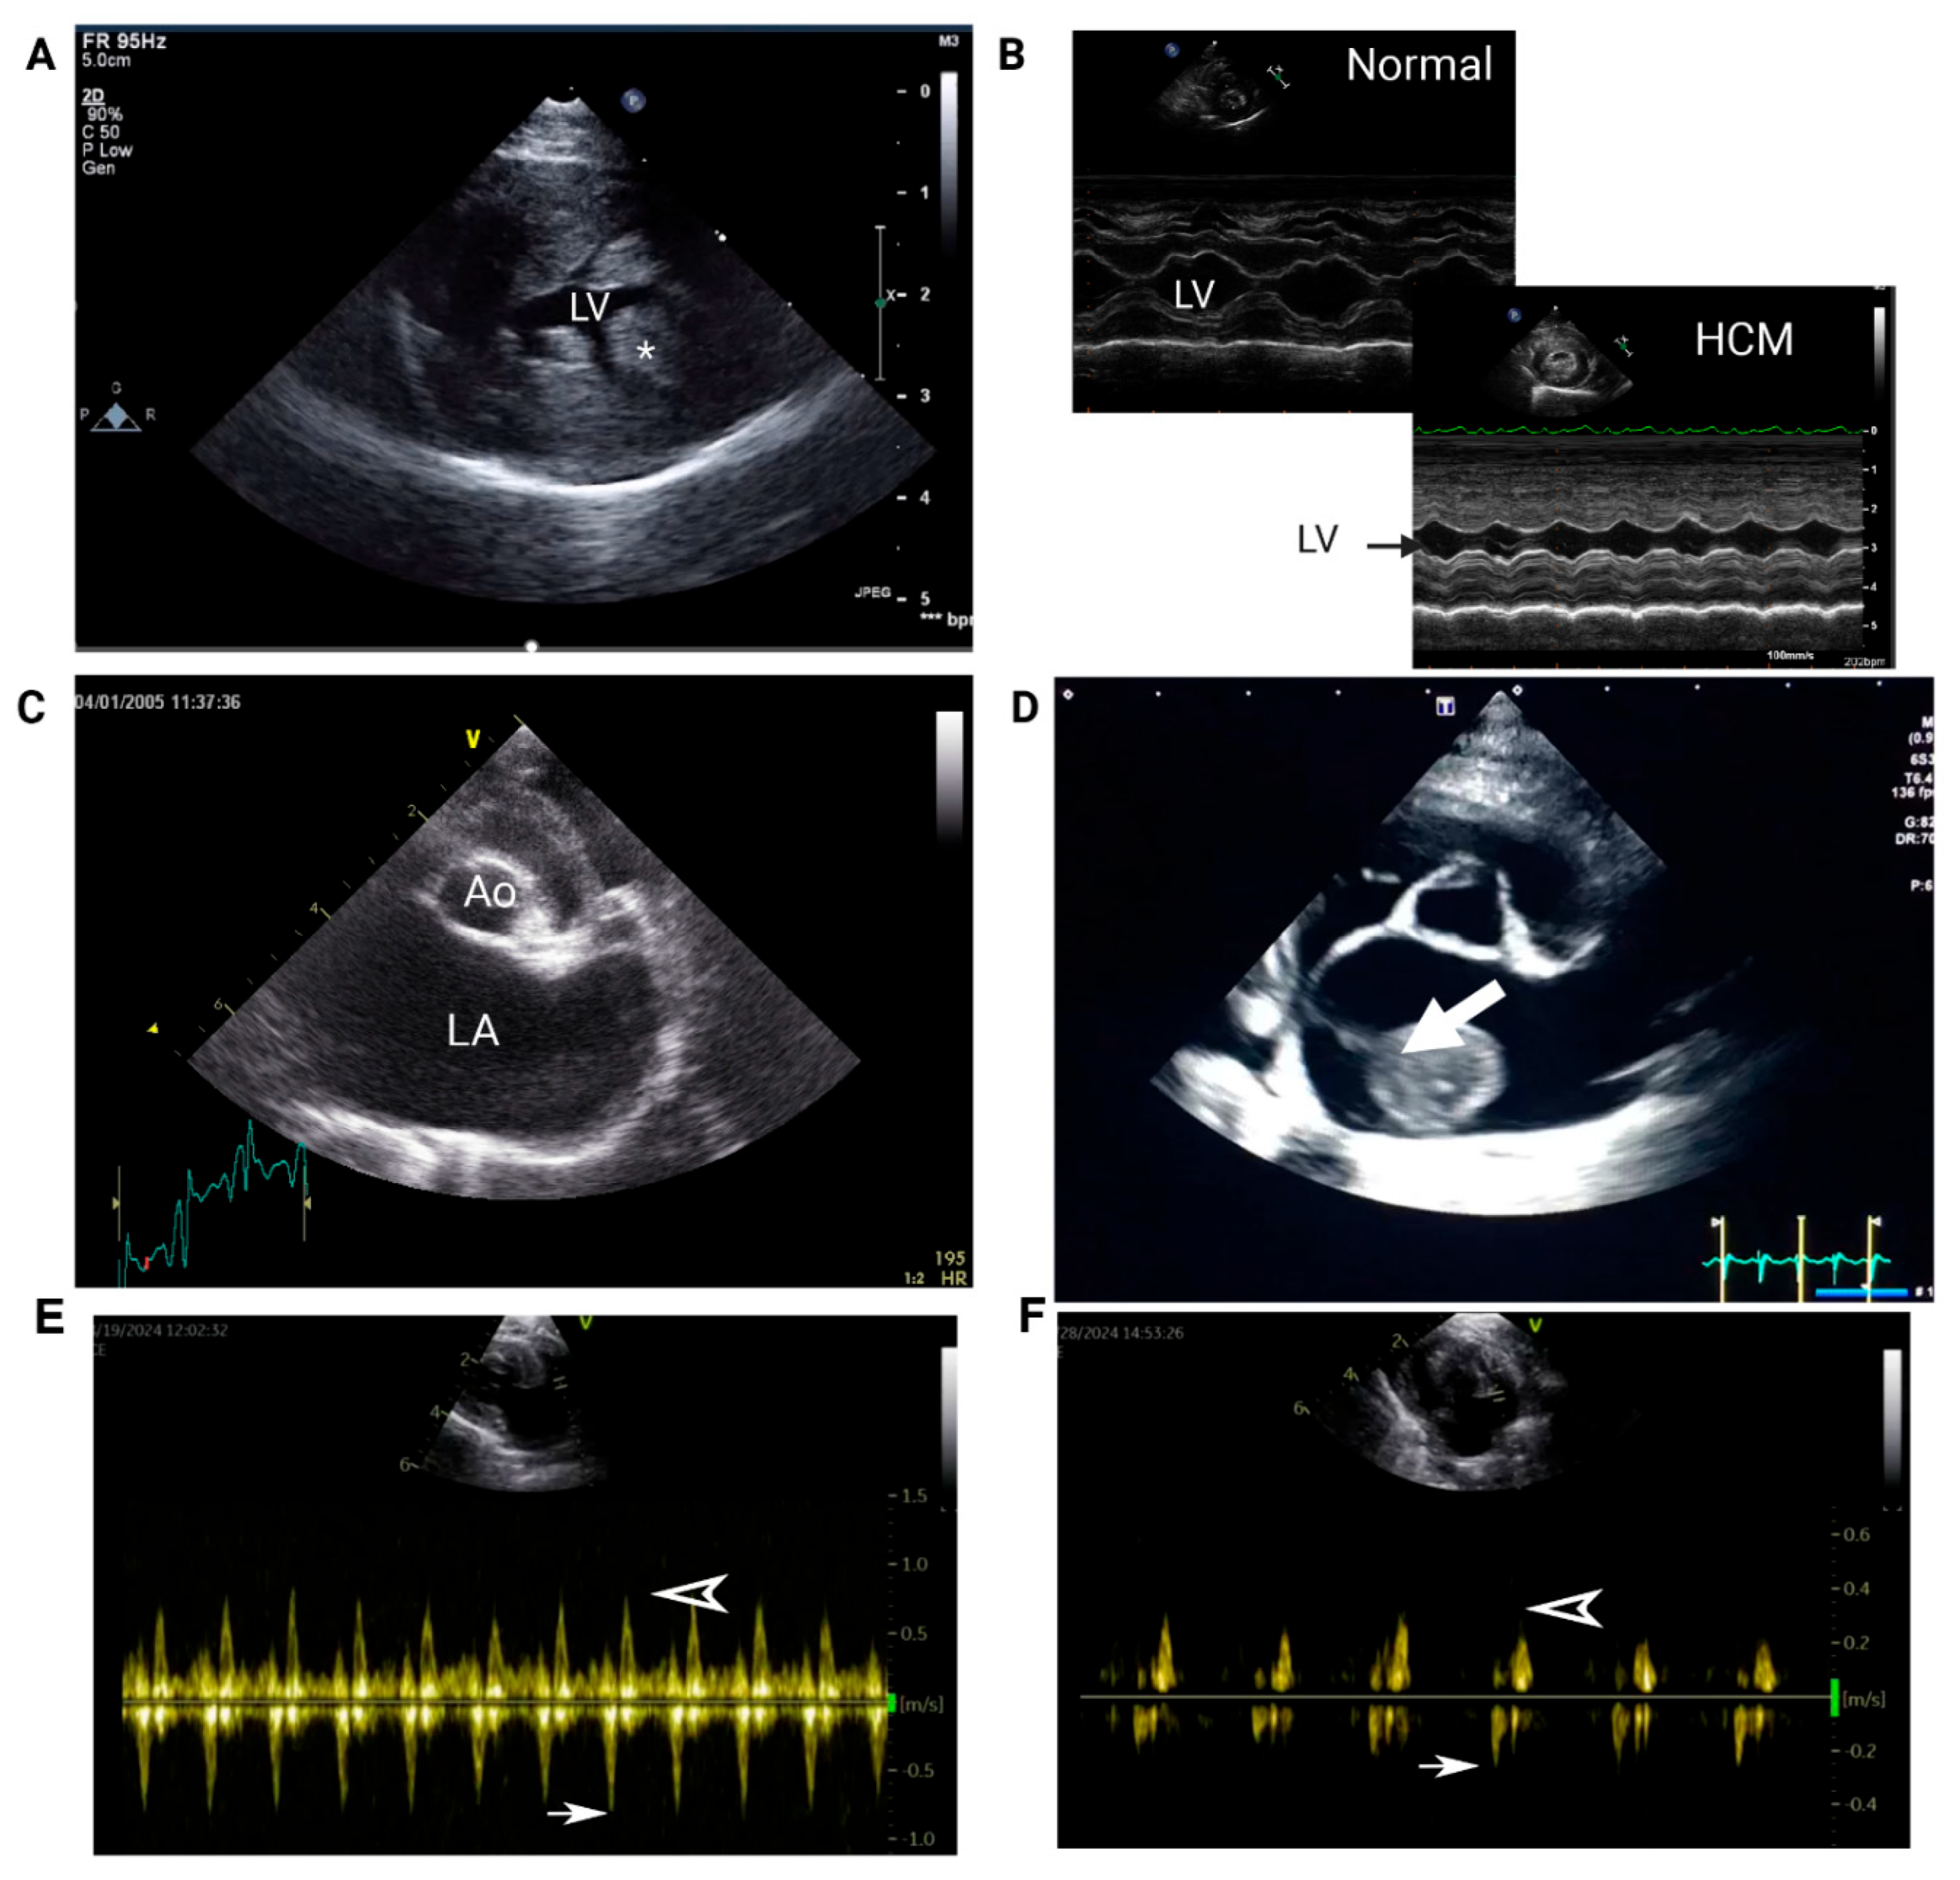

- 1. Echocardiography

| Echocardiogram | LV systolic dysfunction (LV fractional shortening and emptying fraction) |

| LA systolic dysfunction (Low LAA velocity, Low LA fractional shortening) | |

| Spontaneous echocardiographic contrast and/or intracardiac thrombus | |

| LA enlargement (LA:Ao > 1.6) | |